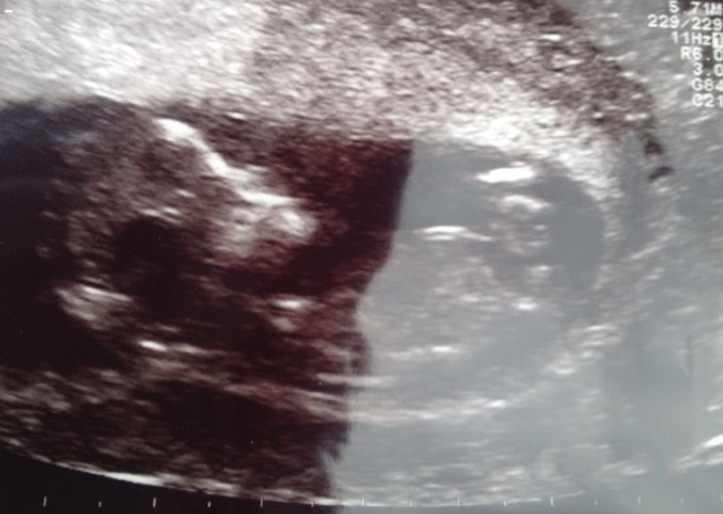

I was told boy by 20 people and now 2 people told me this is

Not the nub..

Any guesses?

Almost 100% that's the nub in the first pic and a boy nub.

Looks like the nub to me, and yep, that's a boy nub!

I'd say that's the nub! Id also say kinda girl... Looks parallel to the spine, I'm no expert tho.

That is definitely the nub and Im leaning slightly more Blue!

Good luck at your scan. I also think it looks like a boy nub

Ya know, I'm not sure on this one. It's kind of in that grey area that could go either way.